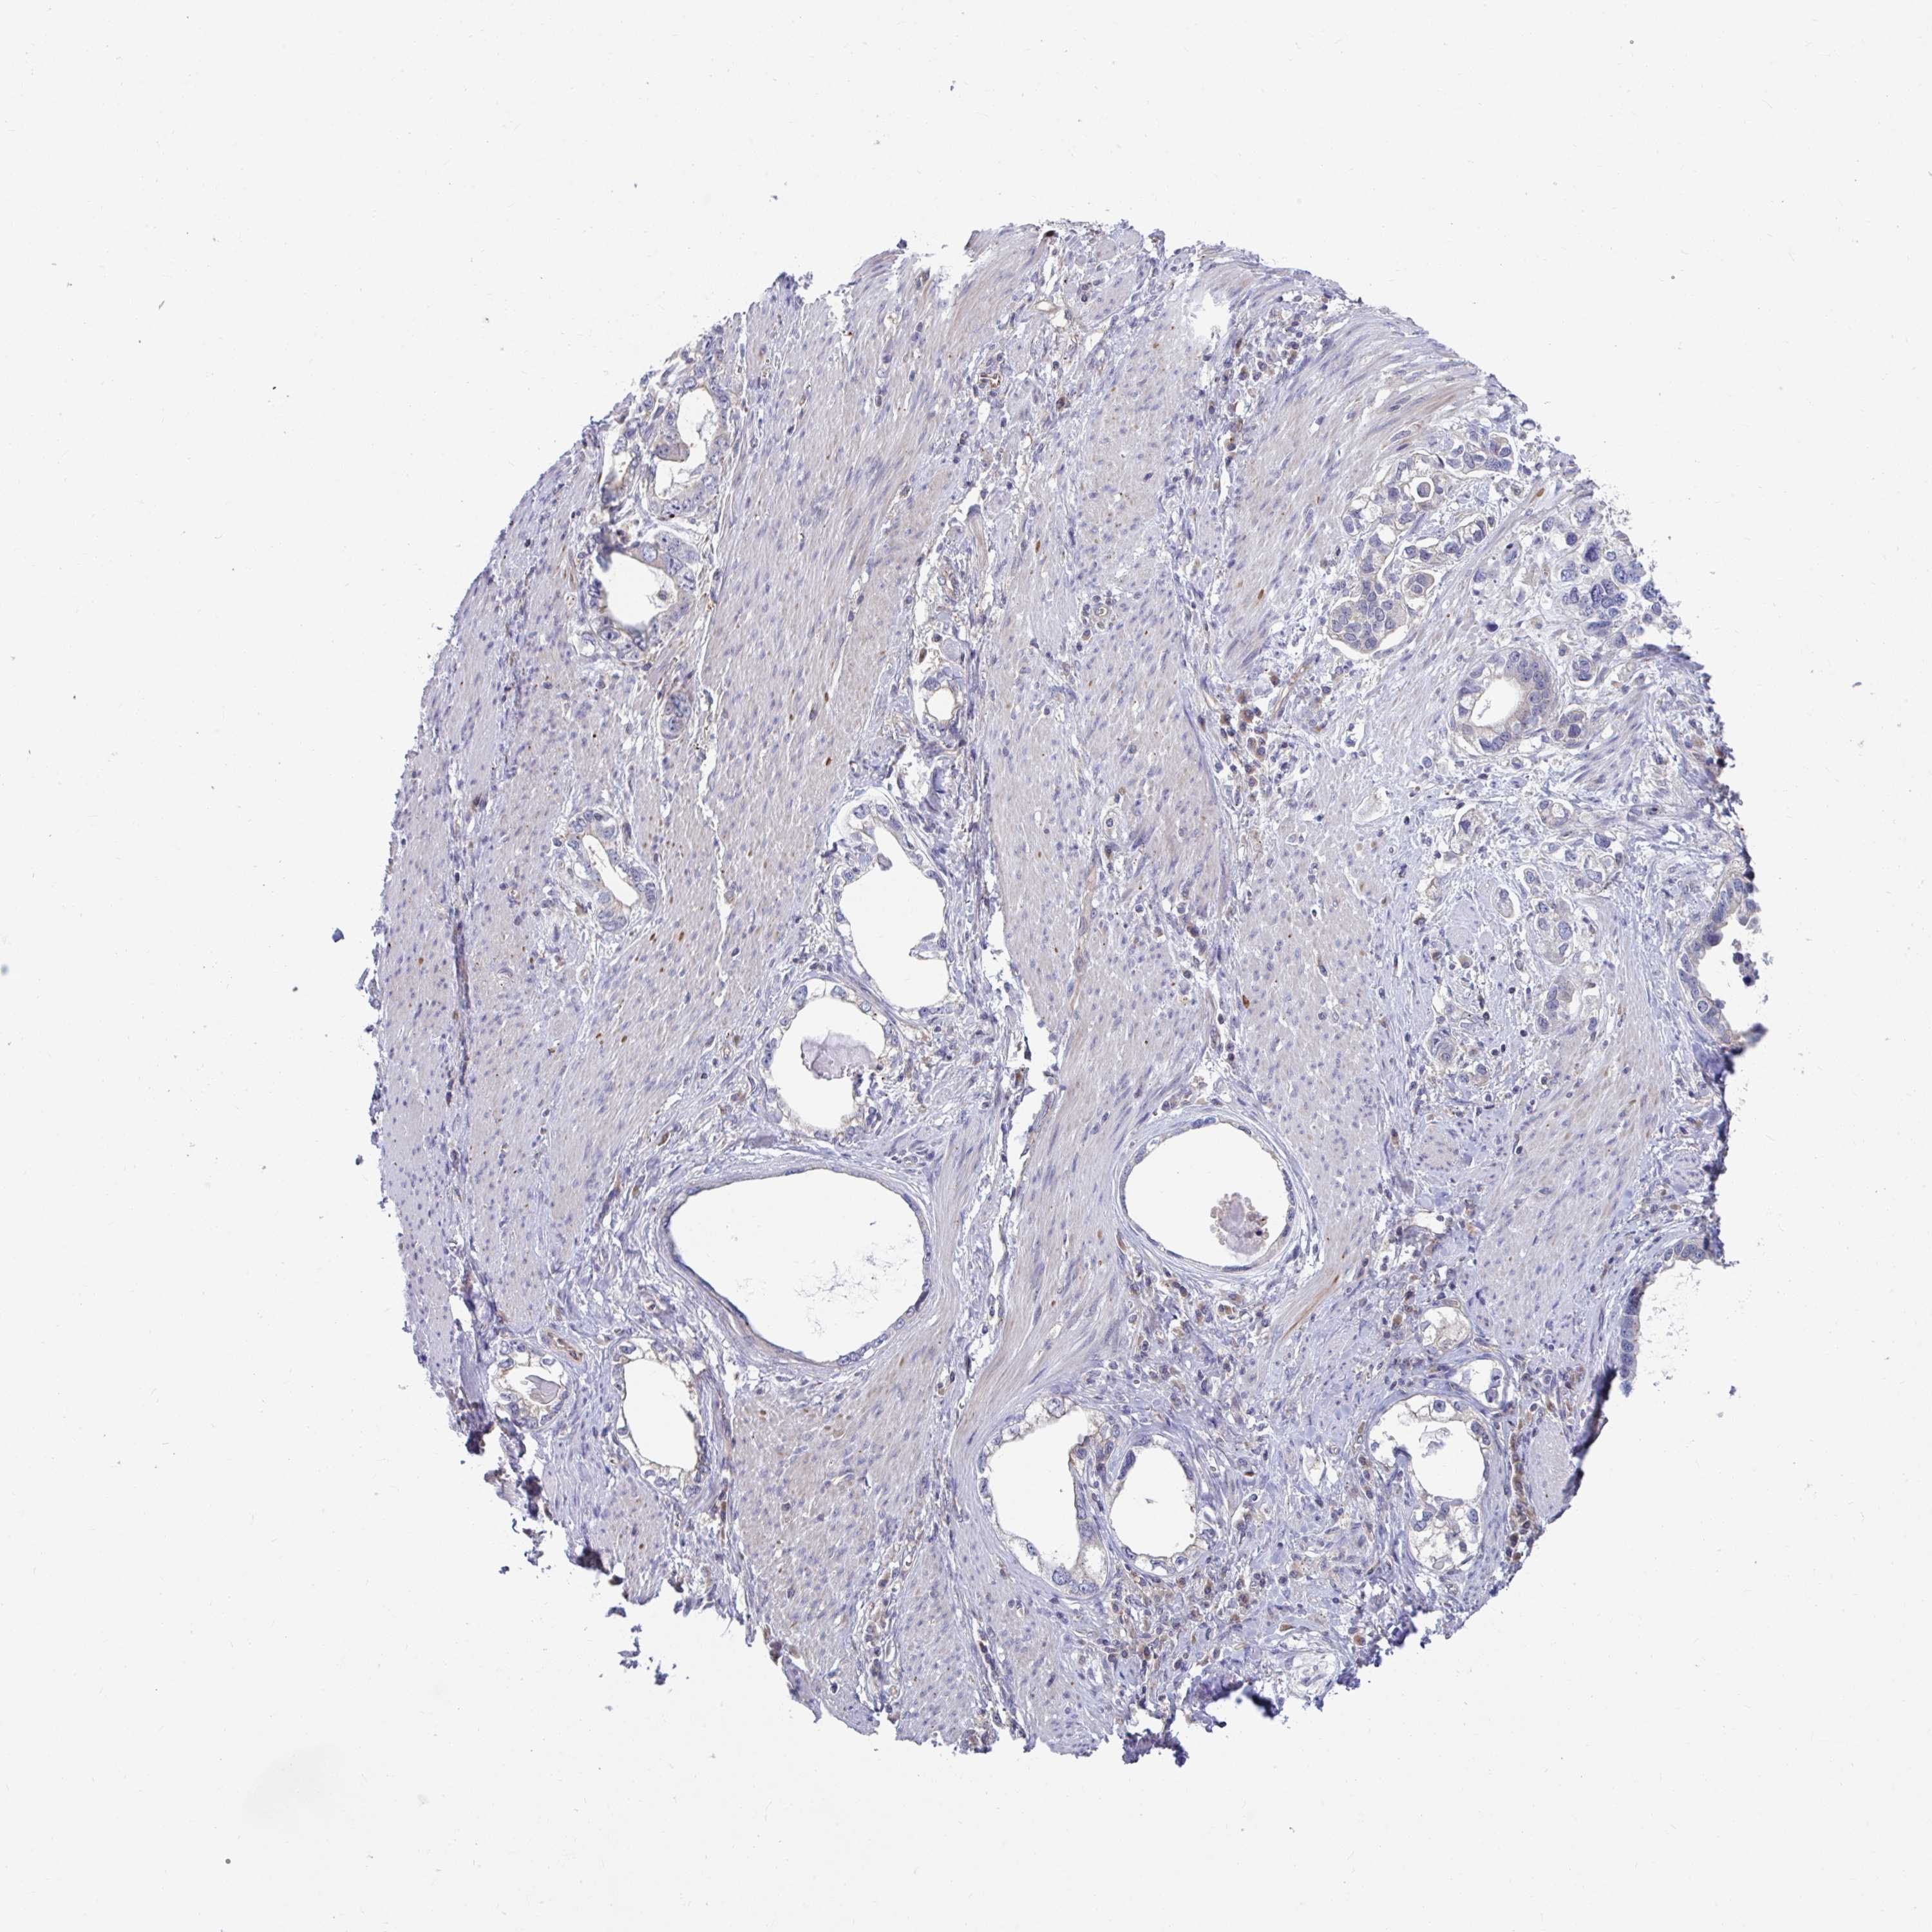

STOMACH CANCER - Protein expressioni

A mouse-over function shows sample information and annotation data. Click on an image to view it in a full screen mode. Samples can be filtered based on level of antibody staining by selecting one or several of the following categories: high, medium, low and not detected. The assay and annotation is described here.

Antibody stainingi

Antibody staining in the annotated cell types in the current human tissue is reported as not detected, low, medium, or high, based on conventional immunohistochemistry profiling in selected tissues. This score is based on the combination of the staining intensity and fraction of stained cells.

Each image is clickable and will lead to virtual microscopy that enables deeper exploration of all samples and also displays staining intensity scores, fraction scores and subcellular localization as well as patient and tissue information for each sample.

Antibody HPA041802

Antibody HPA054532

Adenocarcinoma, NOS

Adenocarcinoma, High grade